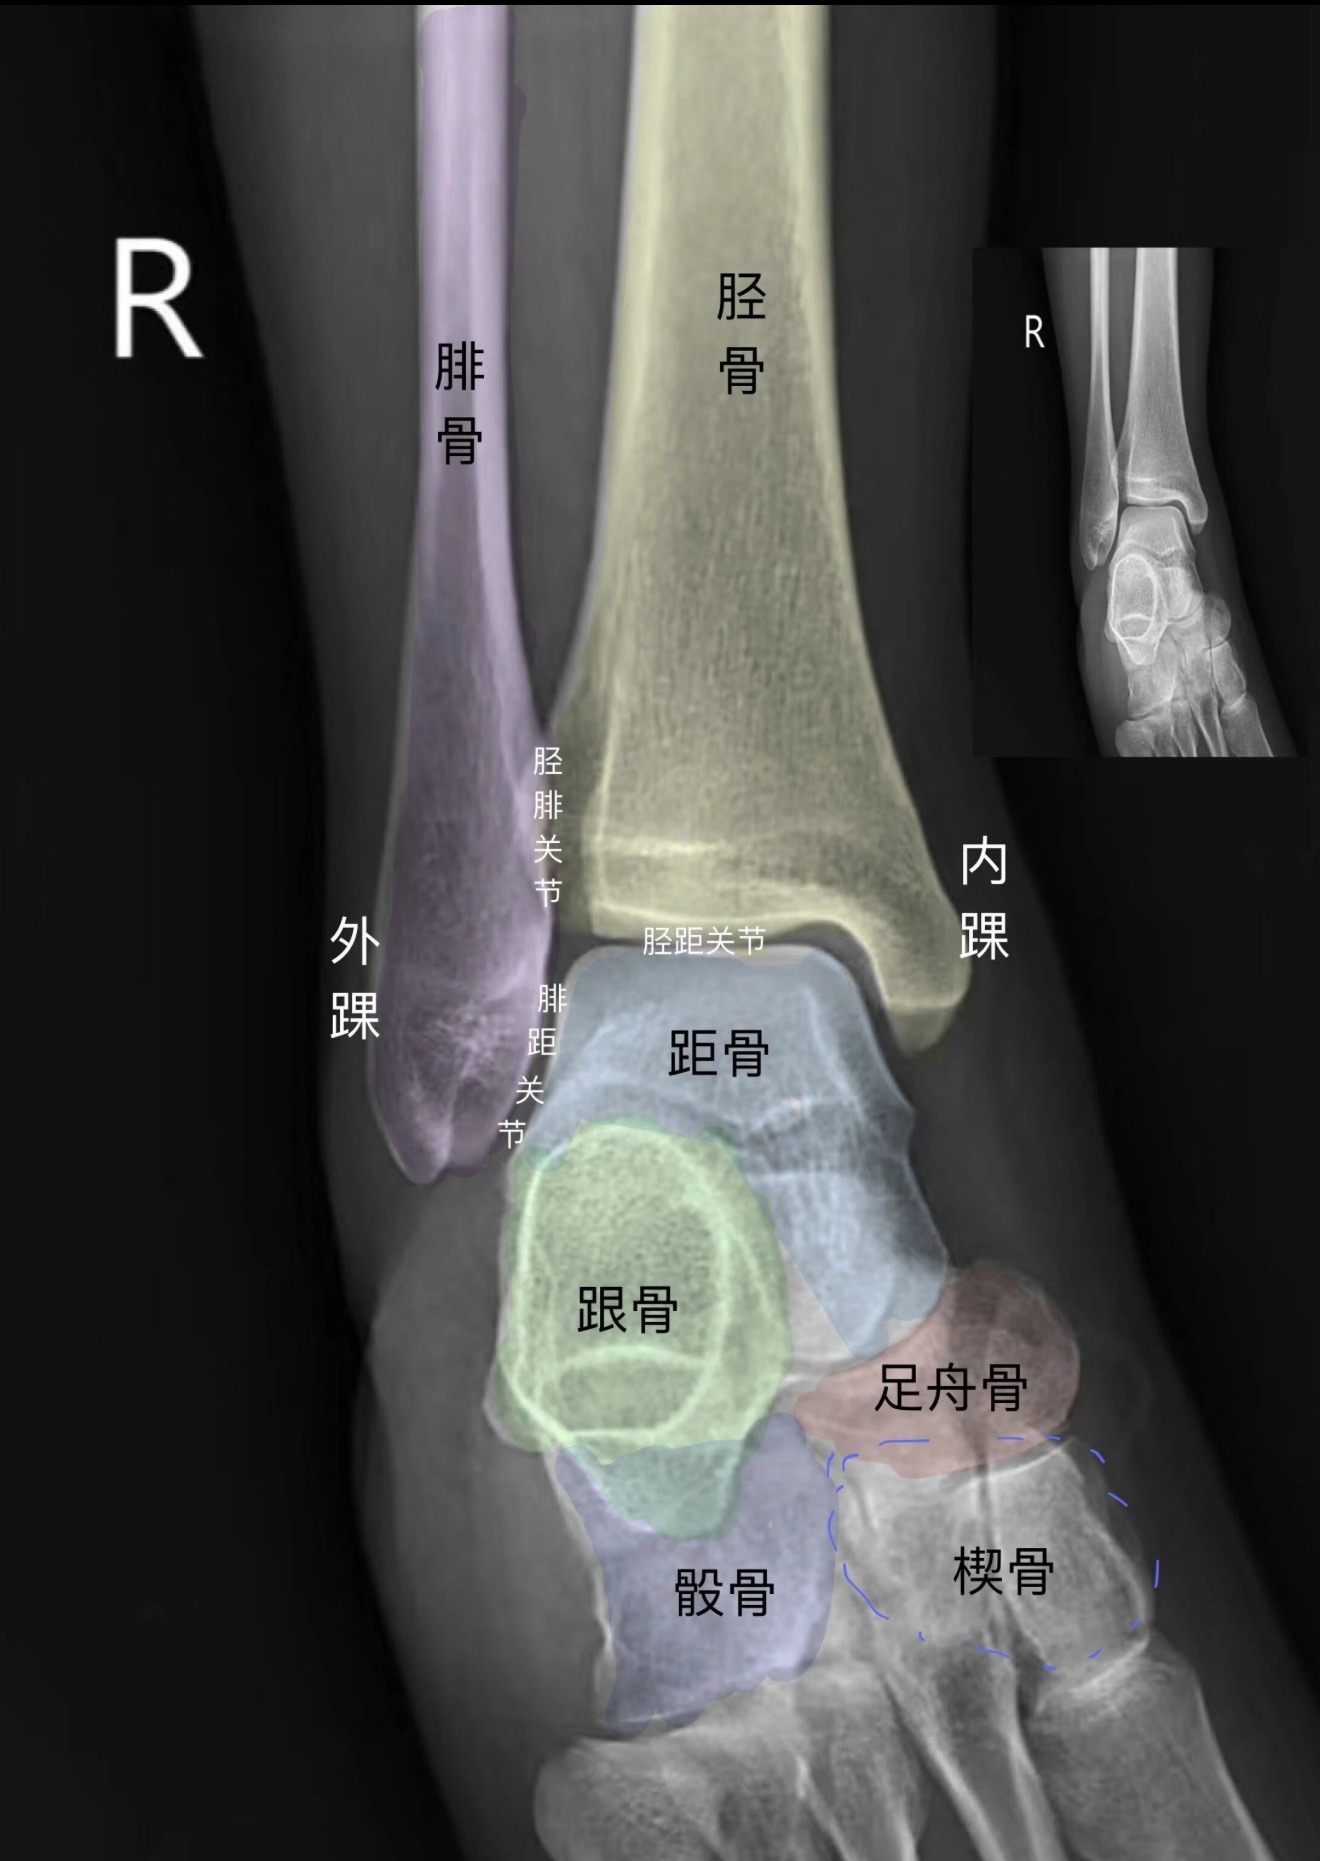

分享DR踝关节正侧位影像图 #医学影像科普#踝关节DR影像解析#DR踝关节解剖